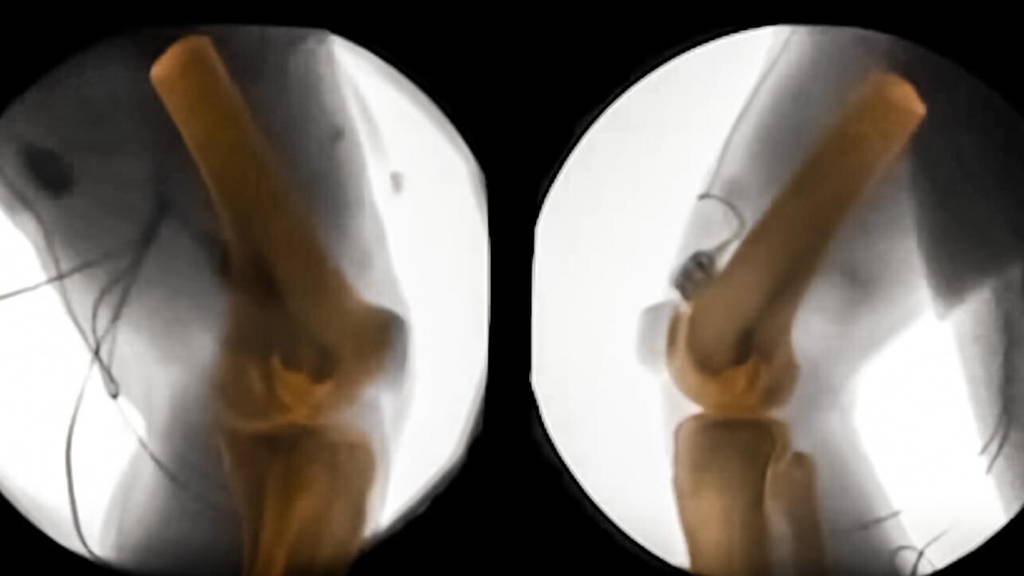

XROMM technology, or X-ray Reconstruction of Moving Morphology, gives researchers a look at bones in motion. This could not only have an impact on human medicine, but also further science’s understanding of animal anatomy. And as if this isn’t enough motivation to advance this technique, the scientists at Brown University also believe that the field of biomechanics could be transformed by it.

X-ray machines have been giving insight into the human body for quite some time now. X-rays can even show movement in unprecedented detail, like blood flowing through a body. One thing such machines can’t provide however, is a 3D-image. Enter CT scans. These scans show detailed, high-quality images of the body in 360 degrees. The scientists at Brown decided to layer these two scans, which led to the XROMM technology and a look at bones in motion.

Understanding how bones move

The new technology helps scientists understand bones more. It, for example, shows how the shape of bones relates to the way the bones move. It also gives scientists a better look at how feet touch the ground, or why prostheses are deemed uncomfortable by amputees. Collaborators at the VA hospital in Providence are already looking at how the residual limb of an amputee moves inside a prosthesis, to try to improve the interface. It could also provide insight as to why women suffer more knee injuries than men. The possibilities seem endless, for humans and animals alike.